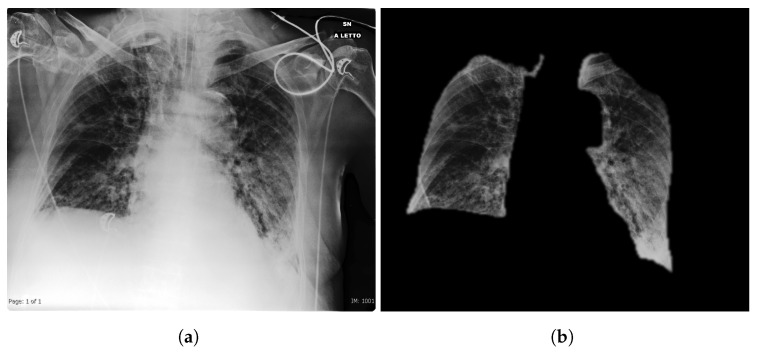

Original image (a) and extracted lung segmented image (b). Many possible bias sources like all the writings and medical equipment is naturally removed.

Tartaglione, Enzo, et al. "Unveiling covid-19 from chest x-ray with deep learning: a hurdles race with small data." International Journal of Environmental Research and Public Health 17.18 (2020): 6933